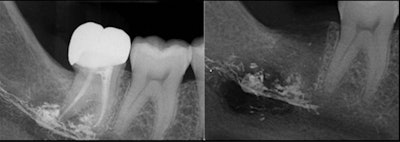

Imaging showed that root canal sealer was widespread within the marrow spaces where endodontic treatment had occurred. The sealer extended to the mandibular canal and perforated the mandible's lingual cortex. There was also evidence of bony destruction and periosteal reaction.

However, pulling the tooth did not resolve the numbness. The patient reported recurrent biting and trauma to her lip, according to the authors. Periapical x-rays taken by the referring oral surgeon showed a radiopaque material at the root tips of tooth #47 and in the mandibular canal area after the tooth was pulled.

A cone-beam computed tomography (CBCT) scan confirmed widespread extrusion of the root canal sealer in this region. Upon surgical exploration and decompression of the woman's right inferior alveolar nerve, clinicians found an avascular and fibrotic nerve with virtually no normal neuronal structure. They also saw evidence of foreign material, which was found to be root canal sealer, in contact with the epineurium and within the nerve trunk.